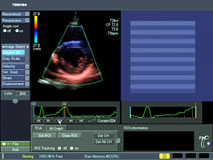

The moving images are transmitted to a monitor and the cardiologist interprets them to see how efficiently your heart is pumping (the ejection fraction), thickness of the muscle walls, or if there are any valve leaks.

Modern cardiac ultrasound systems can provide significant assistance in these analyses -- using color and Doppler studies to help the cardiologist interpret the study.

Aplio echo doppler study

Aplio Tissue Doppler Imaging**